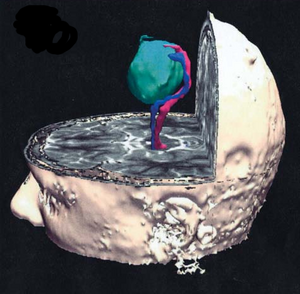

Treatment Planning and Delivery of Whole Brain Irradiation with Hippocampal Avoidance in Rats

Publication: PLoS One. 2015 Dec 4;10(12):e0143208. PMID: 26636762 | PDF Authors: Cramer CK, Yoon SW, Reinsvold M, Joo KM, Norris H, Hood RC, Adamson JD, Klein RC, Kirsch DG, Oldham M. Institution: Department of Radiation Oncology, Duke University Medical Center, Durham, NC, USA. Background/Purpose: Despite the clinical benefit of whole brain radiotherapy (WBRT), patients and physicians are concerned by the long-term impact on cognitive functioning. Many studies investigating the molecular and cellular impact of WBRT have used rodent models. However, there has not been a rodent protocol comparable to the recently reported Radiation Therapy Oncology Group (RTOG) protocol for WBRT with hippocampal avoidance (HA) which is intended to spare cognitive function. The aim of this study was to develop a hippocampal-sparing WBRT protocol in Wistar rats. Methods: The technical and clinical challenges encountered in hippocampal sparing during rat WBRT are substantial. Three key challenges were identified: hippocampal localization, treatment planning, and treatment localization. Hippocampal localization was achieved with sophisticated imaging techniques requiring deformable registration of a rat MRI atlas with a high resolution MRI followed by fusion via rigid registration to a CBCT. Treatment planning employed a Monte Carlo dose calculation in SmART-Plan and creation of 0.5 cm thick lead blocks custom-shaped to match DRR projections. Treatment localization necessitated the on-board image-guidance capability of the XRAD C225Cx micro-CT/micro-irradiator (Precision X-Ray). Treatment was accomplished with opposed lateral fields with 225 KVp X-rays at a current of 13mA filtered through 0.3 mm of copper using a 40x40 mm square collimator and the lead blocks. A single fraction of 4Gy was delivered (2Gy per lateral field) with a 41 second beam on time per field at a dose rate of 304.5 cGy/min. Dosimetric verification of hippocampal sparing was performed using radiochromic film. In vivo verification of HA was performed after delivery of a single 4Gy fraction either with or without HA using γ-H2Ax staining of tissue sections from the brain to quantify the amount of DNA damage in rats treated with HA, WBRT, or sham-irradiated (negative controls). Results: The mean dose delivered to radiochromic film beneath the hippocampal block was 0.52Gy compared to 3.93Gy without the block, indicating an 87% reduction in the dose delivered to the hippocampus. This difference was consistent with doses predicted by Monte Carlo dose calculation. The Dose Volume Histogram (DVH) generated via Monte Carlo simulation showed an underdose of the target volume (brain minus hippocampus) with 50% of the target volume receiving 100% of the prescription isodose as a result of the lateral blocking techniques sparing some midline thalamic and subcortical tissue. Staining of brain sections with anti-phospho-Histone H2A.X (reflecting double-strand DNA breaks) demonstrated that this treatment protocol limited radiation dose to the hippocampus in vivo. The mean signal intensity from γ-H2Ax staining in the cortex was not significantly different from the signal intensity in the cortex of rats treated with WBRT (5.40 v. 5.75, P = 0.32). In contrast, the signal intensity in the hippocampus of rats treated with HA was significantly lower than rats treated with WBRT (4.55 v. 6.93, P = 0.012). Conclusion: Despite the challenges of planning conformal treatments for small volumes in rodents, our dosimetric and in vivo data show that WBRT with HA is feasible in rats. This study provides a useful platform for further application and refinement of the technique. Funding:

MRI with labeled structures from atlas registered to the CBCT. Registration was carried out with the open source imaging tool 3D Slicer, Version 4.4.0. |